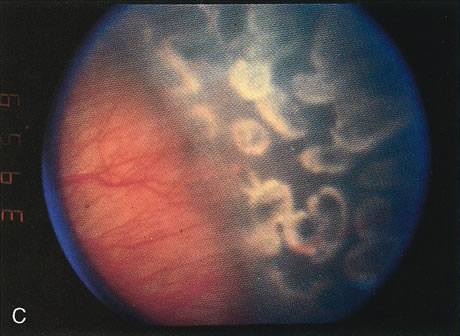

Fig. 6. A. Peripheral neovascularization in zone I. B. Peripheral retina immediately after argon laser photo-coagulation. C. Peripheral retina 1 week after argon laser photocoagulation. D. Peripheral retina 1 month after argon laser photocoagulation. Note the complete regression of neovascularization.